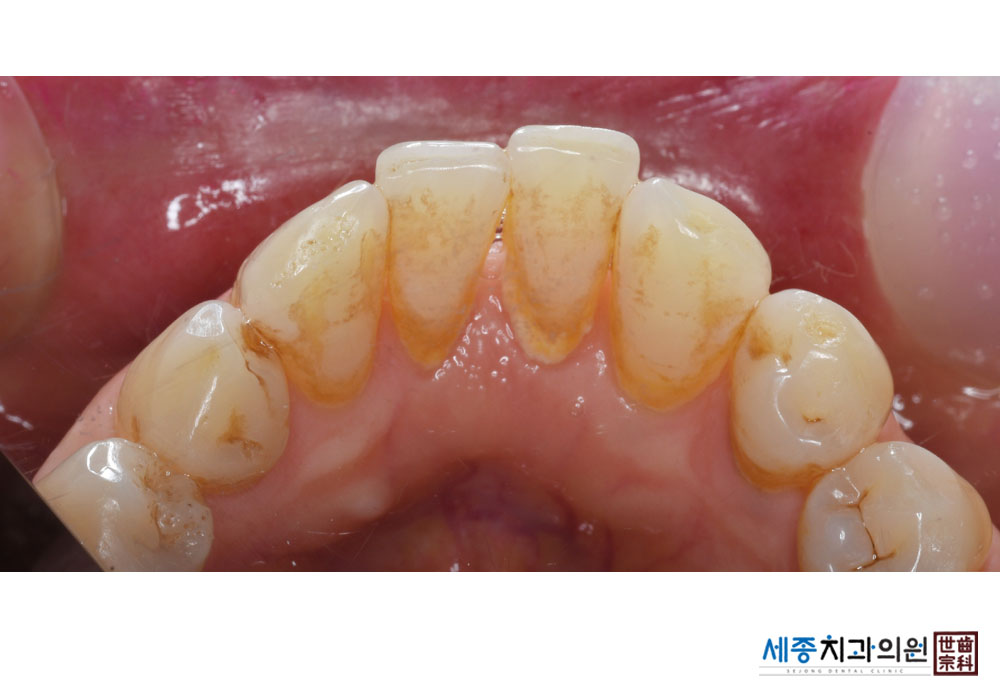

[스케일링] 치주질환 예방 스케일링

치료전 : 2022-05-25

치료후 : 2022-05-25

가글마취&저주파 스켈러를 사용한 스케일링